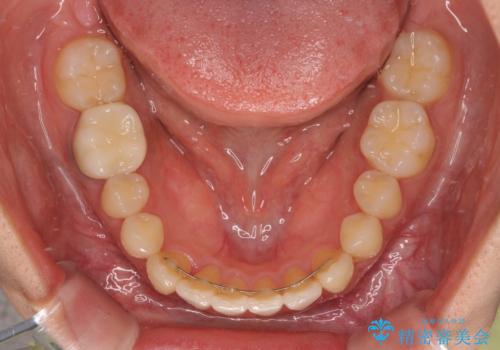

下顎前歯にデコボコが集中していたため、顎間ゴムによる後方移動とIPR(歯と歯の間を削ること)により歯列を整えることとしました。

しっかりとマウスピースを装着してくださったおかげで、スムーズに治療を終えることができました。

矯正治療途中で右下奥歯の虫歯治療を近医で行ったようで、既に神経が失活していたと合わせて矯正治療後に補綴治療を行う予定です。